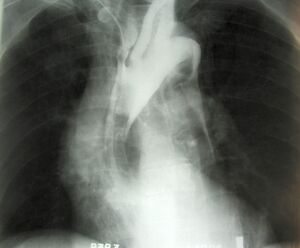

image الإنجليزية

Aneurysem.jpg

٥٢٠ × ٤٨٨؛ ١١٦ كيلوبايت

media legend الإنجليزية

Angiography of an aneurysm in a brain artery. The aneurysm is the large bulge in the center of the image. (الإنجليزية)